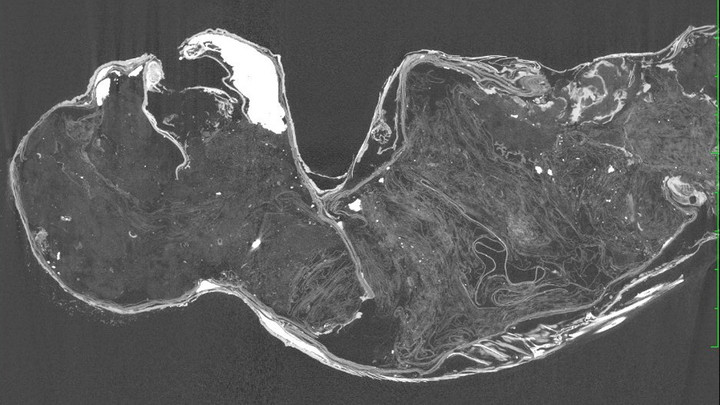

Ảnh chụp X-quang và CT của xác ướp "nàng tiên cá" ở đền Enjuin bốc trần sự thật về truyền thuyết về sinh vật này. (Ảnh: KUSA)

Cụ thể, kết quả cho thấy phần thân của “nàng tiên cá” không thuộc về bất kỳ loài linh trưởng nào mà chủ yếu được làm từ vải, giấy và bông được giữ với nhau bằng các chốt kim loại chạy từ cổ xuống lưng. Nó cũng được phủ một lớp sơn bằng hỗn hợp cát và than củi để tạo cảm giác nhìn giống như một xác ướp.

Ngoài ra phần thân “nàng tiên cá” được đắp lên bởi các bộ phận từ các động vật khác như lông và da cá của động vật có vú, có thể là từ một con cá nóc với các bộ phận như cánh tay, vai, cổ và má. Hàm và răng của “nàng tiên cá” cũng có khả năng được lấy từ một loài cá săn mồi và móng vuốt của nó được làm từ chất sừng, có nghĩa là chúng có thể đến từ một loài động vật có thật nhưng không thể xác định được loài nào.

Nửa dưới của “nàng tiên cá” được lấy từ một loài cá, có khả năng là một loài cá đù - một họ cá thuộc bộ Cá vược sống ngoài biển và phân bố ở vùng biển nhiệt đới, cận nhiệt đới.

Các nhà nghiên cứu KUSA không thể xác định bất kỳ DNA hoàn chỉnh nào của “nàng tiên cá”, nhưng việc xác định niên đại bằng carbon phóng xạ từ vảy cho thấy chúng có thể có niên đại từ đầu những năm 1800.